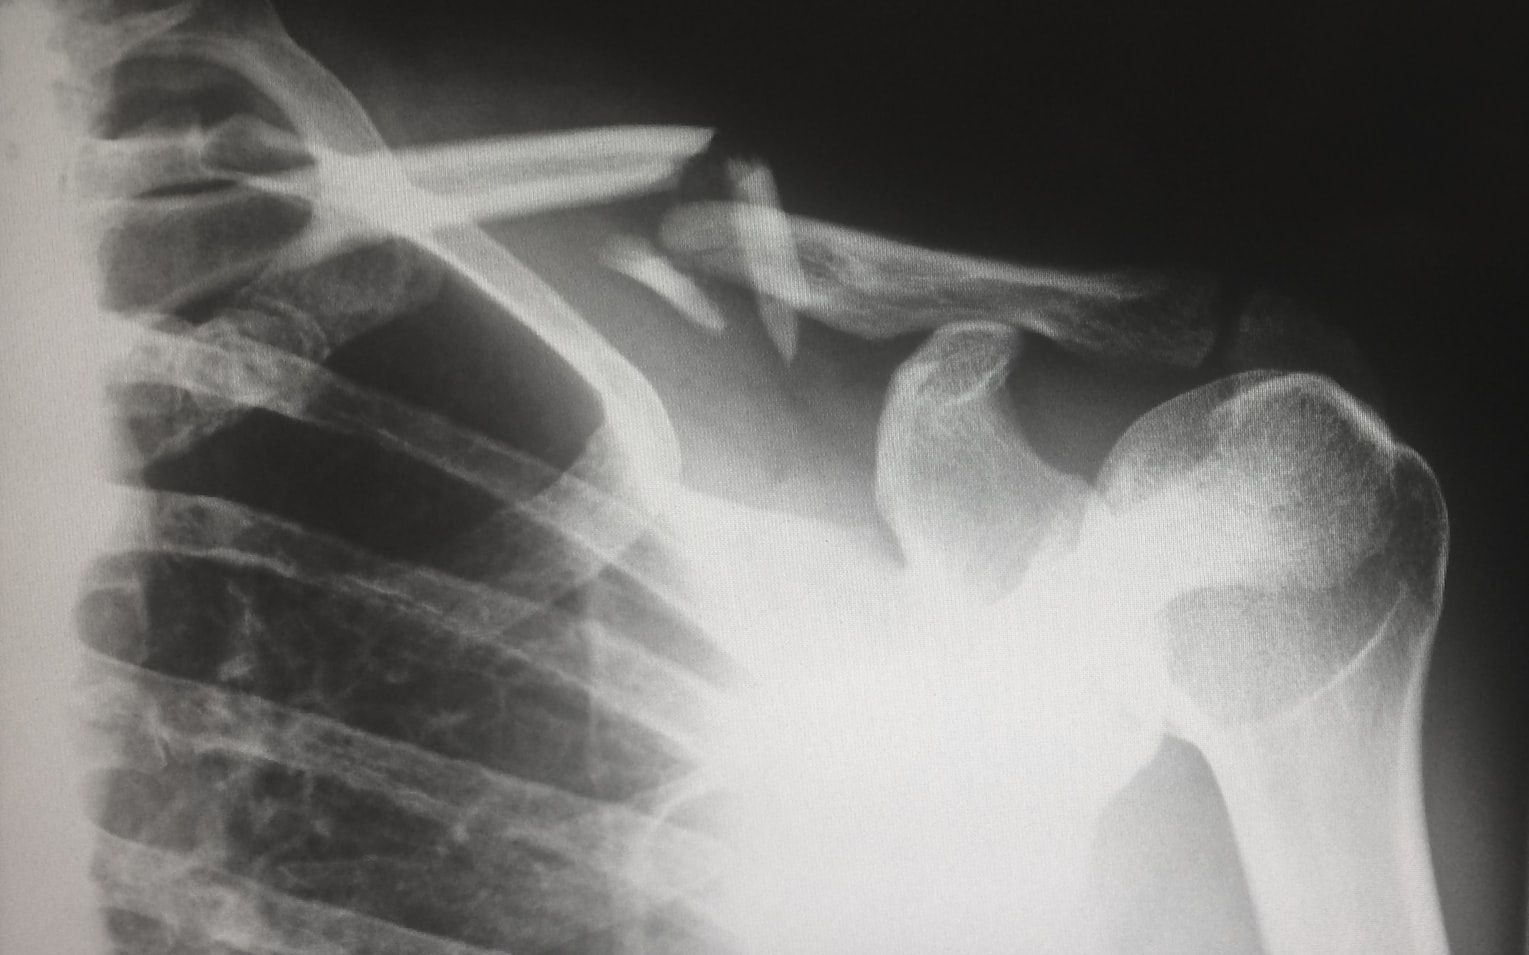

Your bones can grow horns

Image: Alessandro La Becca

Osteomas are benign bone tumors that can sometimes protrude through the skin, resembling small "horns." Most appear on the skull or jaw.

Though rare, some osteomas can grow several inches. Surgical removal is usually performed for cosmetic reasons unless the growth interferes with normal function.